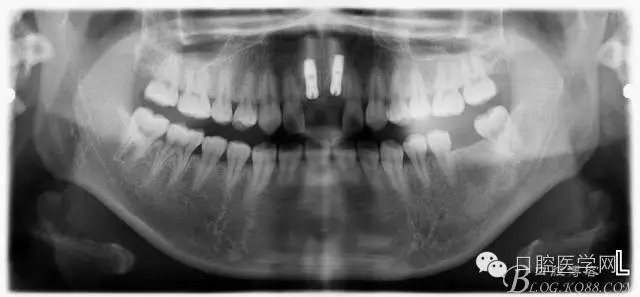

設計方案:11.21種植(選用登騰系統(tǒng),GBR植骨)12.22 RCT后樁冠修復,牙齦瓷修復。

一期手術后3-6個月可做二次修復,接愈合基臺,拆線后10-15天根據(jù)情況可以采模型做牙冠。